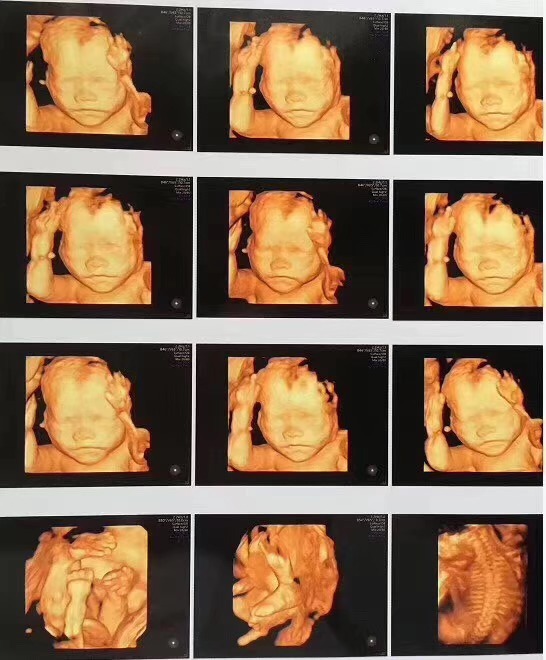

四维彩超约起!宝妈不要错过检查~

孕妈妈们想知道宝宝在肚子里干什么吗?

想知道宝宝长什么样子吗?

想知道宝宝发育健康吗?

答:一般来说,孕22-26周是做四维彩超最佳的时间,因为这个时候胎宝宝的肢体和主要脏器都已经发育,加上羊水适中,能够看清胎宝宝各个部位的生长发育情况,对体表进行排畸检查,孕妈们可不要错过时候哦。

答:许多孕妈妈都很期待做四维彩超,因为这是准妈妈和BB的“第一次”见面,能够看到ta在肚子里或活泼或文静的可爱模样。但四维彩超更重要的作用是能够监测到胎宝宝的健康情况,进行排畸检查。